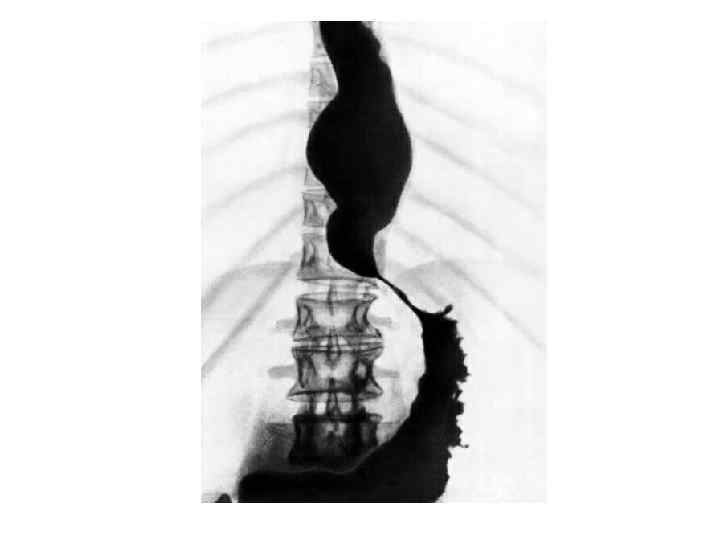

Классификация ахалазии • I тип характеризуется умеренным сужением дистального отрезка пищевода и незначительным супрастенотическим расширением пищевода (до 6 см). Сохраняется его цилиндрическая или овальная форма. • При ахалазии II типа отмечается выраженное сужение дистальной части пищевода и его значительное супрастенотическое расширение (иногда до 16 18 см), из за чего пищевод часто принимает N образную форму. В зависимости от вида дискинезии грудного отдела пищевода выделяют гипермоторную и гипомоторную формы ахалазии кардии, а в зависимости от тяжести клинического течения заболевания стадии компенсации и декомпенсации.

Стадии (рентгенологически) I – коническое сужение, барий быстро попадает в желудок II – расширение в грудной части пищевода, в которой скапливается жидкость III – резкое расширение пищевода. Опорожнение пищевода задерживается на несколько суток

Классификация (Масевич Ц. Г. , 1995) 1) функциональный спазм пищевода без растяжения; 2) постоянный спазм пищевода, умеренное расширение и сохраненная перистальтика; 3) рубцовые изменения стенки с выраженной дилатацией пищевода, перистальтика отсутствует; 4) значительное растяжение пищевода с S-образным удлинением и наличие эрозивных изменений слизистой оболочки пищевода.

Ахалазия пищевода II III стадии